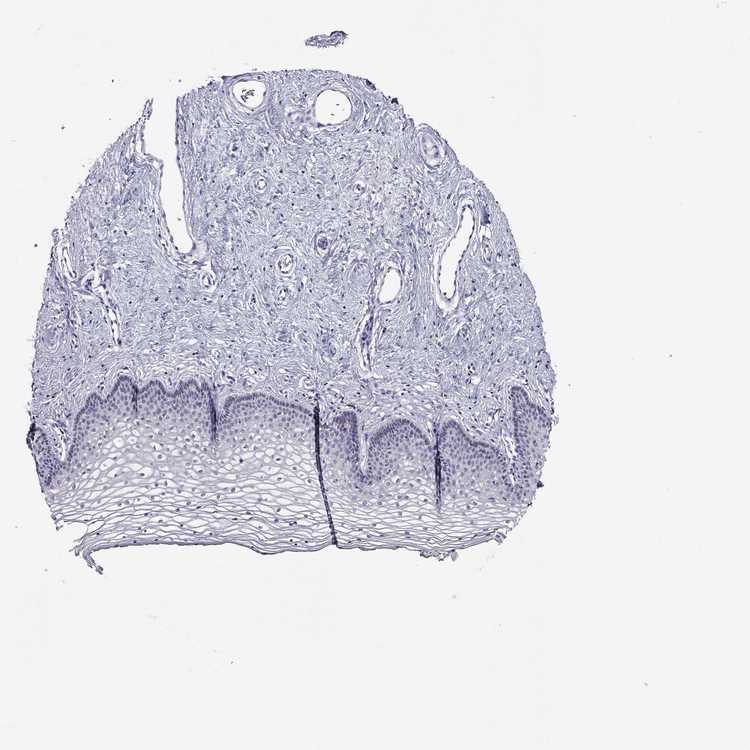

TISSUE PRIMARY DATA VAGINA Show tissue menu

VAGINA - Antibody stainingi

Antibody staining in the annotated cell types in the current human tissue is reported as not detected, low, medium, or high, based on conventional immunohistochemistry profiling in selected tissues. This score is based on the combination of the staining intensity and fraction of stained cells.

Each image is clickable and will lead to virtual microscopy that enables deeper exploration of all samples and also displays staining intensity scores, fraction scores and subcellular localization as well as patient and tissue information for each sample.

Antibody HPA017931Antibody HPA020289

Squamous epithelial cells Not detectedNot detected